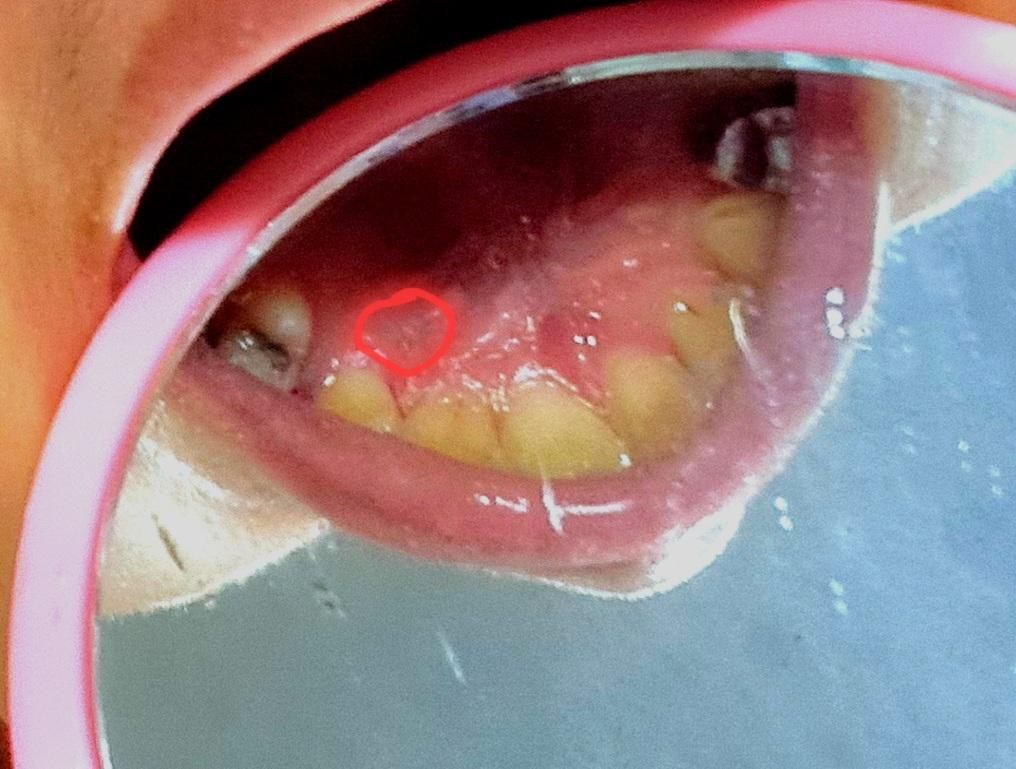

앞 송곳니 잇몸 안에 뭐가 나오고 있는 건가요?

어제 혀로 앞니들을 핥아봤는데

송곳니 옆쪽에 뾰족한게 만져져서 봤더니 뼈같은

딱딱한 것이 만져졌어요, 이건 있는지도 몰랐습니다

아무리 검색해도 잘 안뜨고 골융기라고 뜨네요

• 1번 째 사진

공융기라면 치조골이 자라 나와 있는 것이기 때문에 문제가 되지는 않습니다. 하지만 치아에 있는 감염으로 인한것이라면 치료가 필요할수 있습니다.

해당부위는 구개골융기 내지는 과잉치 같습니다 ct찍어보면 좋을 것 같습니다 냅둬도 될 수도 있고 제거가 필요할 수도 있습니다

골융기로 보이지는 않습니다. 엑스레이 사진을 찍어봐야 무엇인지 유추할 수 있어보입니다.

윗부분은 골융기는 아닌거 같으니 치과에 가셔서 사진을 찍고 확인을 받아보시는게 좋을것같습니다.